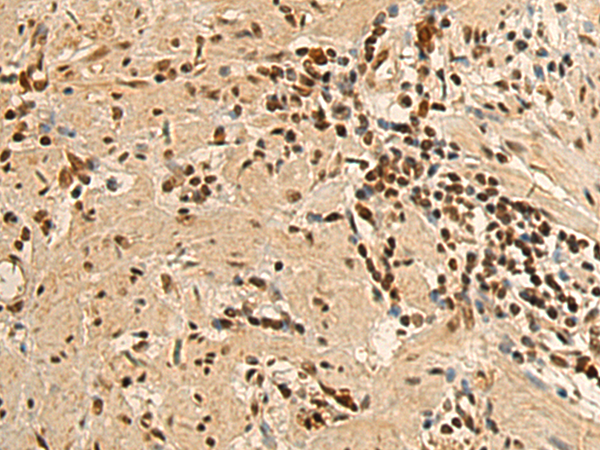

分类: 科研抗体货号: P08705别名: RIP5; RIPK5; CAKUT1; DustyPK; HDCMD38P应用: WB,IHC反应种属: Human